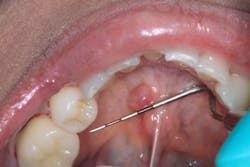

Clinical assessment reveals a red, tissue-colored, raised, fluctuant mass on the left side of the lingual frenum, in the area of the submandibular gland duct. There is a slight tenderness to palpation with some firmness to the lesion overall. The mass measures approximately 4 mm x 5 mm in length (see photos below).